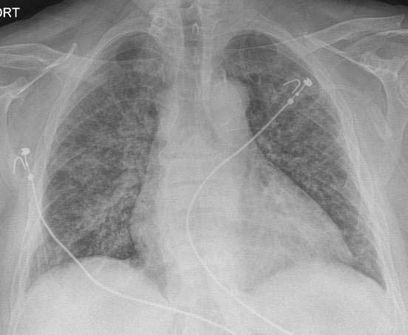

Стандартная РГ имеет низкую чувствительность в выявлении начальных изменений в первые дни заболевания и не может применяться для ранней диагностики. Информативность РГ повышается с увеличением длительности течения пневмонии. Рентгенография с использованием передвижных (палатных) аппаратов является основным методом лучевой диагностики патологии ОГК в отделениях реанимации и интенсивной терапии (ОРИТ). Применение передвижного (палатного) аппарата оправдано и для проведения обычных РГ исследований в рентгеновском кабинете. В стационарных условиях относительным преимуществом РГ в сравнении с КТ являются большая пропускная способность. Метод позволяет уверенно выявлять тяжелые формы пневмоний и отек легких различной природы, которые требуют госпитализации, в том числе направления в ОРИТ.

5. Рекомендовано проведение лучевого исследования пациентам при среднетяжелом, тяжелом и крайне тяжелом течении ОРИ с целью медицинской сортировки, оценки характера изменений в грудной полости и определения прогноза заболевания:

- выполнение РГ легких в двух проекциях, если проведение КТ в данной медицинской организации/клинической ситуации невозможно.

8. Рекомендовано проведение лучевого исследования пациентам с тяжелым и крайне тяжелым течением ОРИ, требующим лечения в условиях ОРИТ:

- оптимально: выполнение экстренной РГ легких в ОРИТ с использованием передвижного (палатного) аппарата;

10. Оценка динамики пневмонии COVID-19 в ОРИТ проводится по клиническим показаниям:

- возможно: выполнение РГ с помощью передвижного (палатного) рентгеновского аппарата;